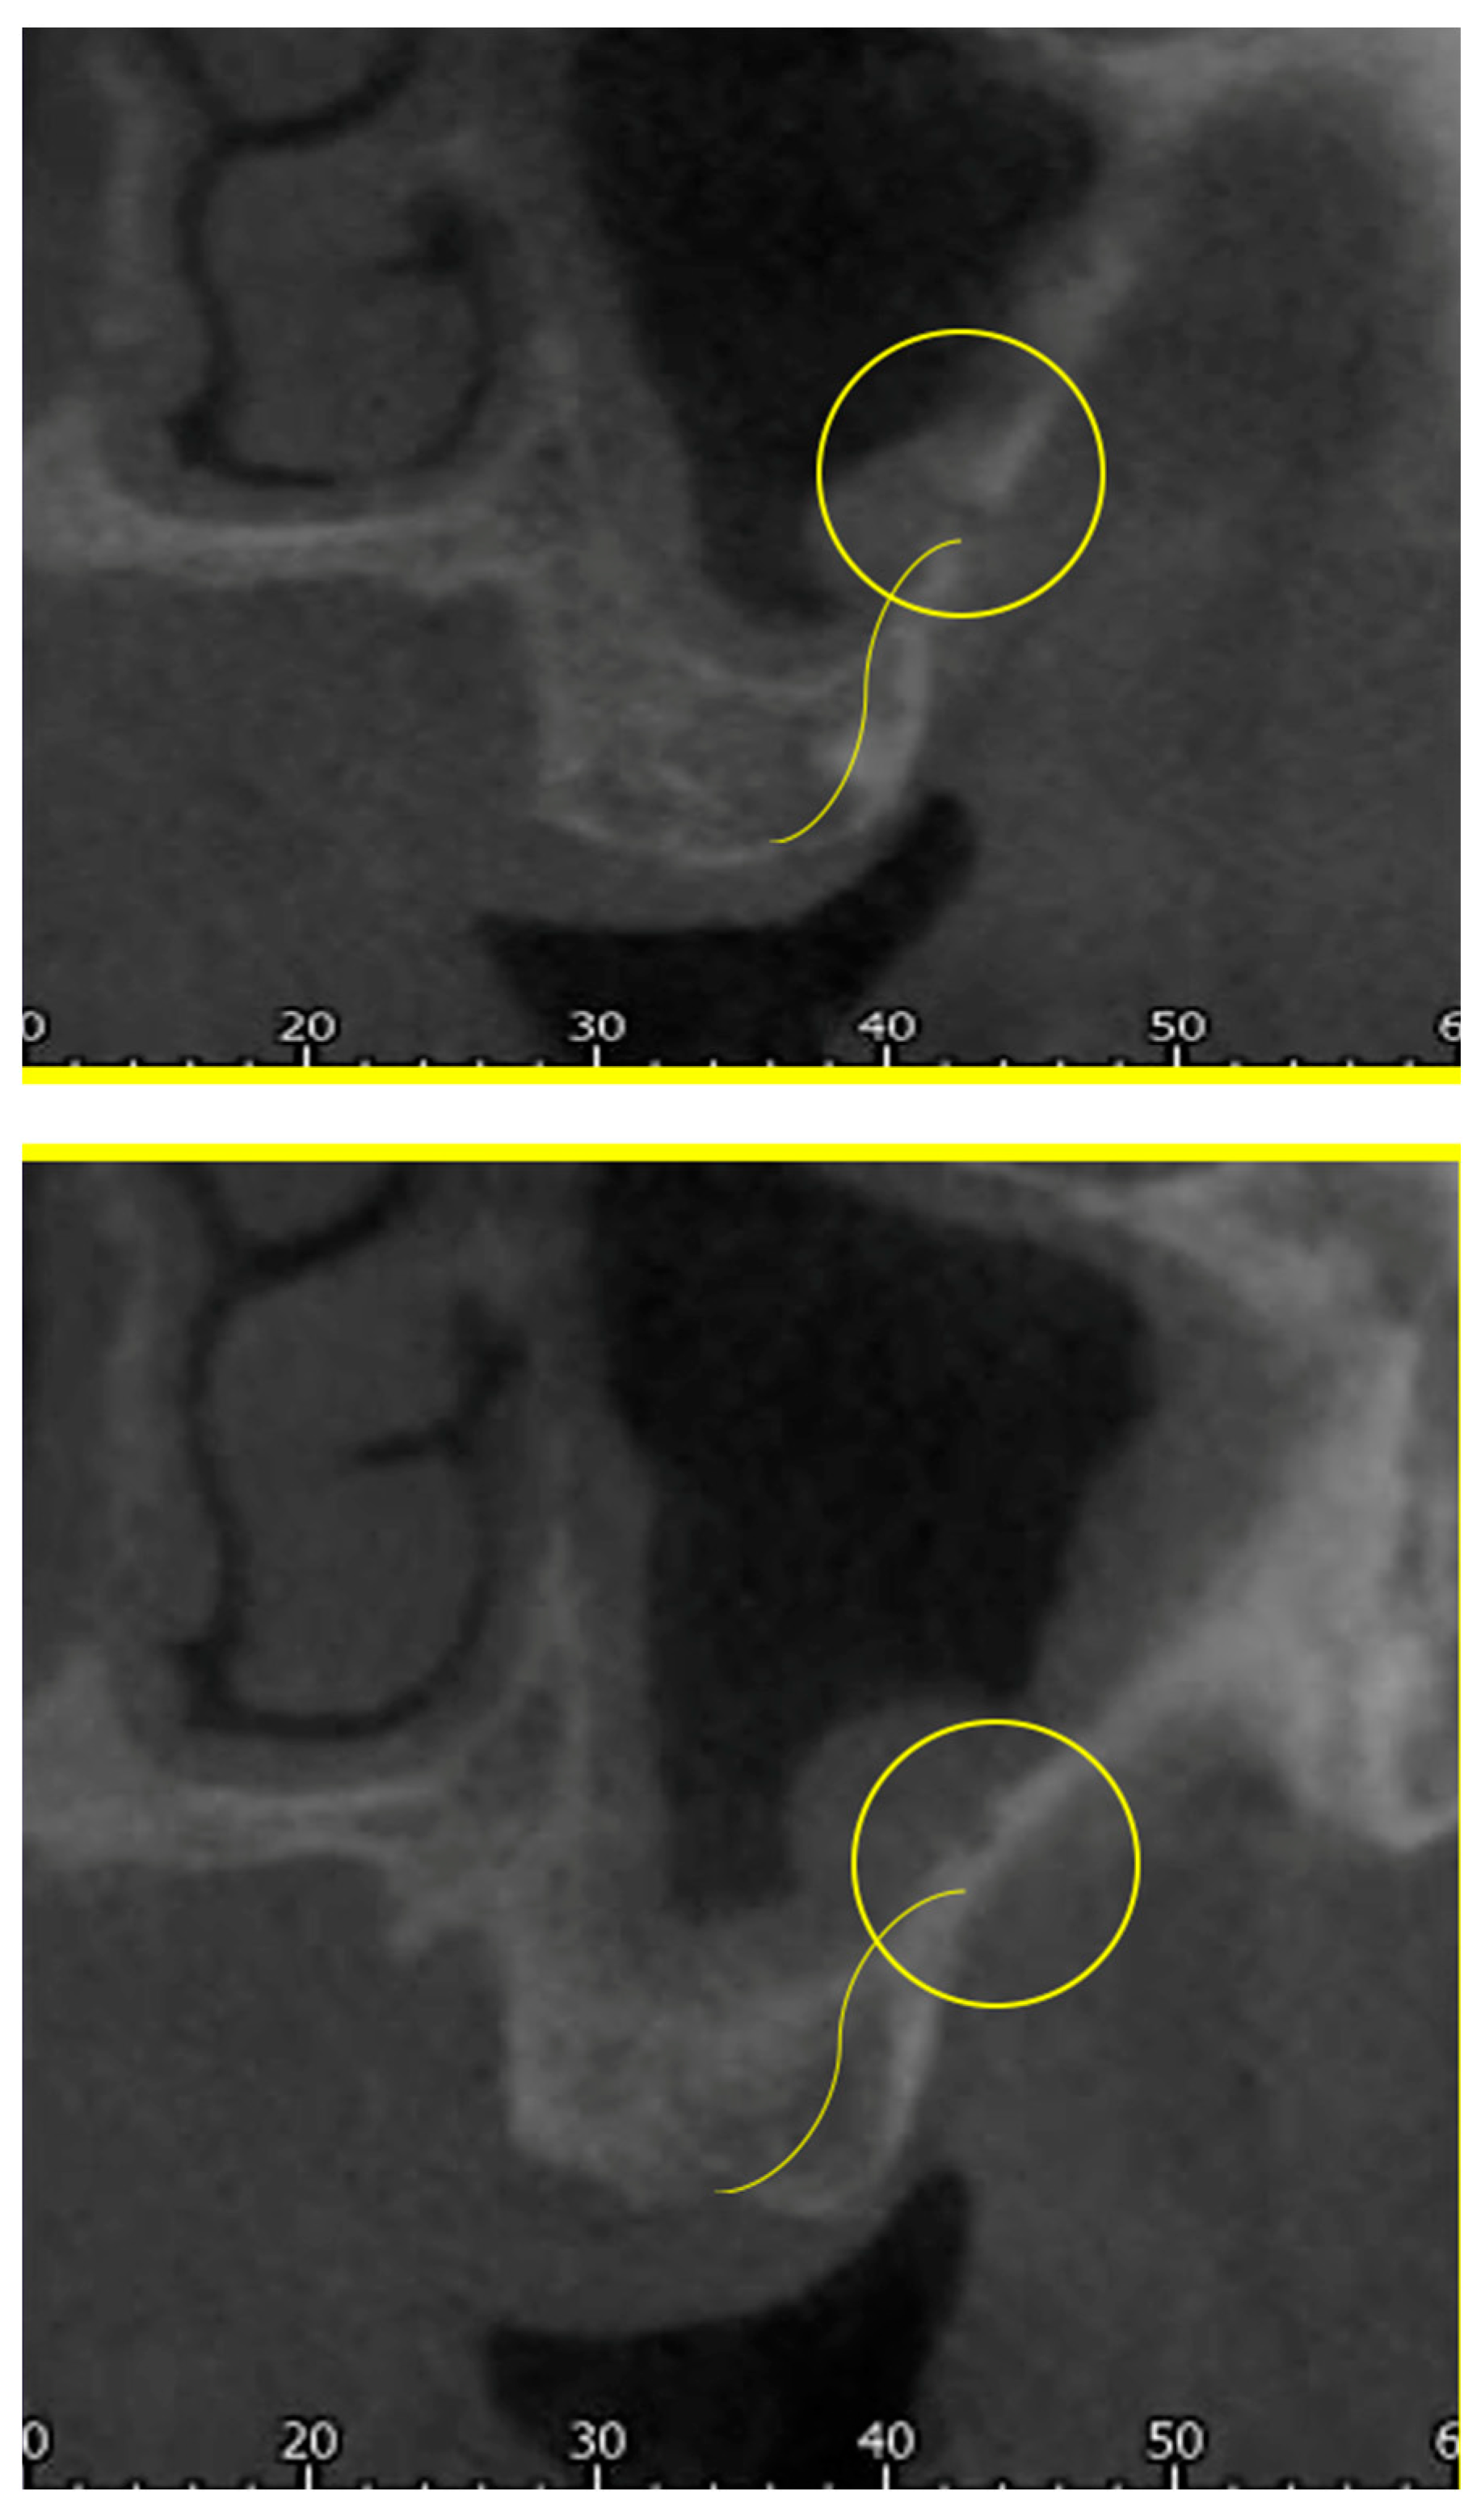

- The length of the arterial pathway in the mesiodistal dimension, on cross-section setting at 1 mm (Figure 2);

- The height of the maxillary bone crest in the cranio-caudal direction, on cross-section at the level of the first superior molar (Figure 3);